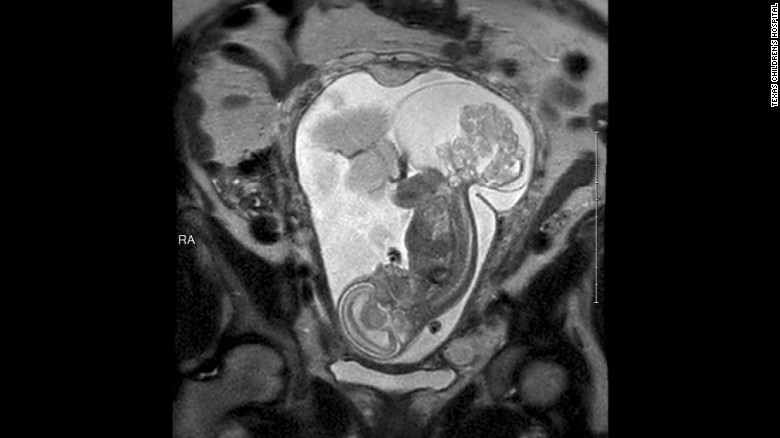

The tumor threatening LynLee's life can be seen in this ultrasound. Sacrococcygeal Teratoma is found more often in girls than boys.

Sacrococcygeal teratoma is a tumor that develops before birth and grows from a baby's coccyx, the tailbone.

She was 23 weeks and 5 days pregnant, when Cass performed the emergency fetal surgery. By this time, the tumor was nearly larger than the fetus.